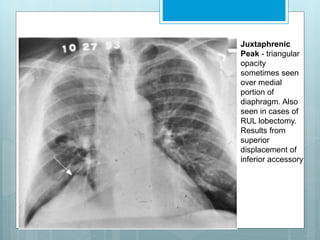

Juxtaphrenic

Peak - triangular

opacity

sometimes seen

over medial

portion of

diaphragm. Also

seen in cases of

RUL lobectomy.

Results from

superior

displacement of

inferior accessory